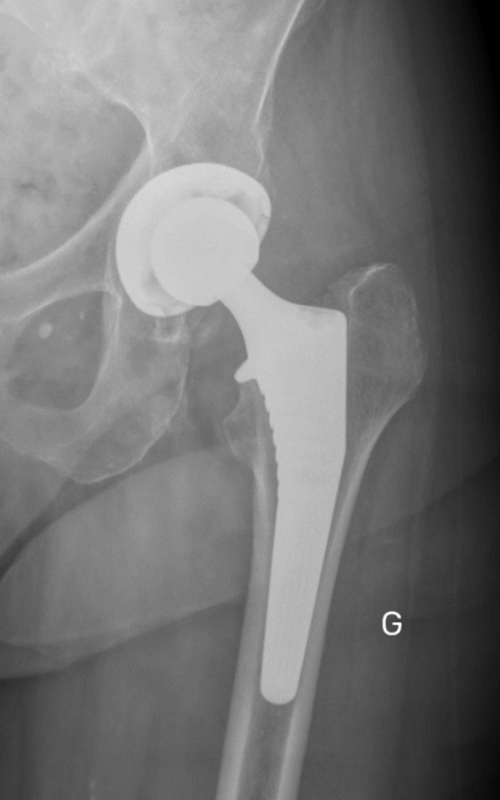

Pour les cas plus avancés où la douleur et la perte de fonction sont significatives, la chirurgie de remplacement de la hanche, également appelée prothèse de hanche, peut être envisagée. Cette intervention chirurgicale peut grandement améliorer la qualité de vie en rétablissant la mobilité et en soulageant la douleur.

La récupération après une intervention chirurgicale de remplacement de la hanche peut varier en fonction du patient et de la procédure spécifique. Cependant, avec des soins post-opératoires appropriés, la plupart des patients retrouvent progressivement leur mobilité et leur qualité de vie.